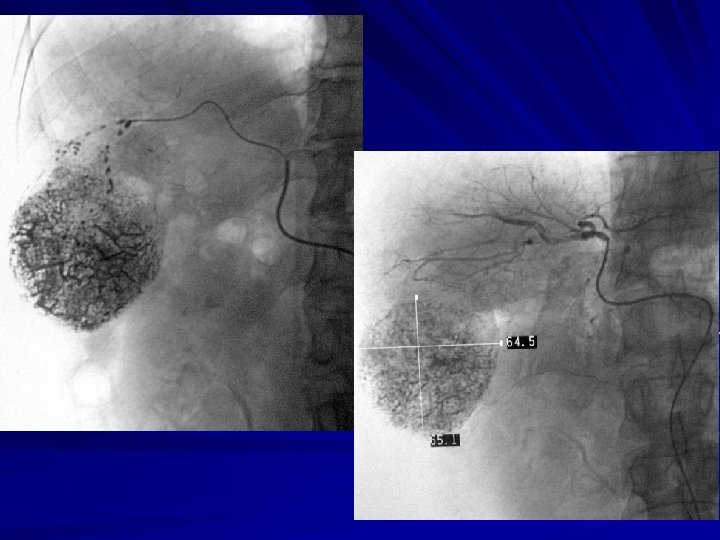

RESULT-4 Angiography characteristics : (1) hypertrophy of the feeding OAs were noted in 28 patients (n=28) ; (2) OAs’ edges are untidily and rigidity (n=11) , huge HCC compressed gastroduodenal artery and it’s branches displaced were noted ; (3) defective tumor staining or defective lipiodol deposit in 7 patients (n=7).

Discussion -2 2、Angiography characteristics of HCC fed by OA. n Position: Generally,OA originated from the gastroduodenal artery or pancreaticoduodenal artery arch ,distributed in the greater omentum ,As long as there is retinal tissue coverage, Any segment of the HCC liver may occur OA parasitic blood supply. n In our study,we found that any segment of the liver may occur OA parasitic blood supply,except S 2;But the most common occurred in the right lobe and left lobe.

Abdominal enhanced CT :the edge of the tumor arterial thickening, strongly indicate the presence of parasitic OA blood vessel.

Use of microcatheter—TACE